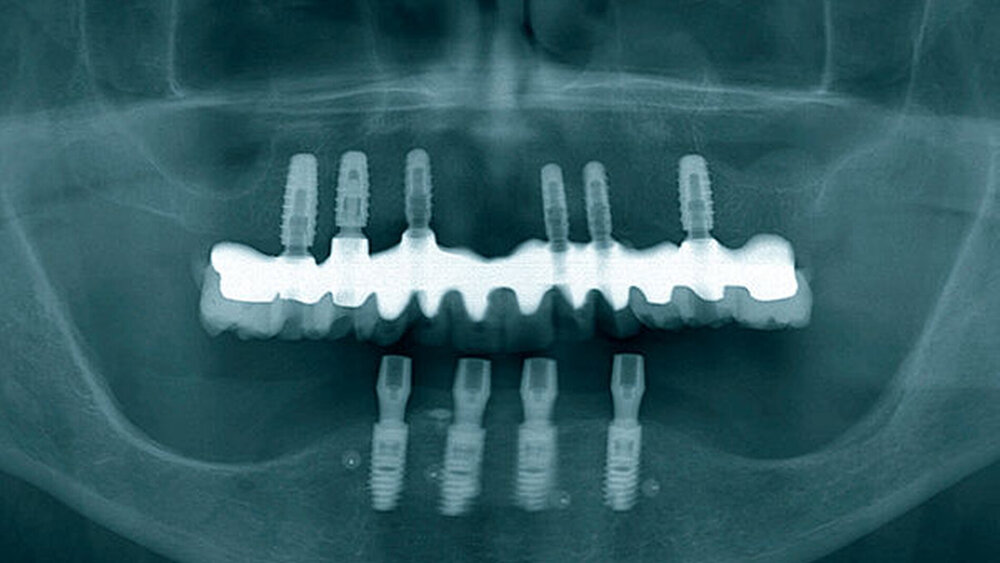

Die dreidimensionale Positionierung und die richtige Anordnung der Implantate sowie des Zahnersatzes. Es ist wichtig, eine prächirurgische prothetische An- und Sprechprobe (Set-up) durchzuführen, um die Implantatpositionen und -achsen korrekt nach der späteren Prothetik zu bestimmen und auszurichten.

Das hat nichts mit den unterschiedlichen Protokollen zu tun. Der Übergang zwischen Restauration und dem Abutment darf nicht sichtbar sein, egal bei welchem Protokoll. Entweder werden die Implantate deshalb tiefer gesetzt oder der Knochen wird abgetragen. Unproblematischer ist das im Unterkiefer, die Lippe und die Lippenbänder verdecken viel. Wir implantieren – wann immer das geht – erst in der 3er-, 4er-, 5er-Position, nicht direkt in der Front.

Eine 67 Jahre alte Patientin stellte sich mit dem Wunsch einer Oberkiefersanierung in unserer Praxis vor. Ihre Restzähne waren aufgrund von Parodontitis und funktioneller Überlastung nicht mehr erhaltungswürdig. Wir ließen sie bis kurz vor der definitiven Versorgung als strategische Pfeilerzähne für die Interimsprothese in situ.